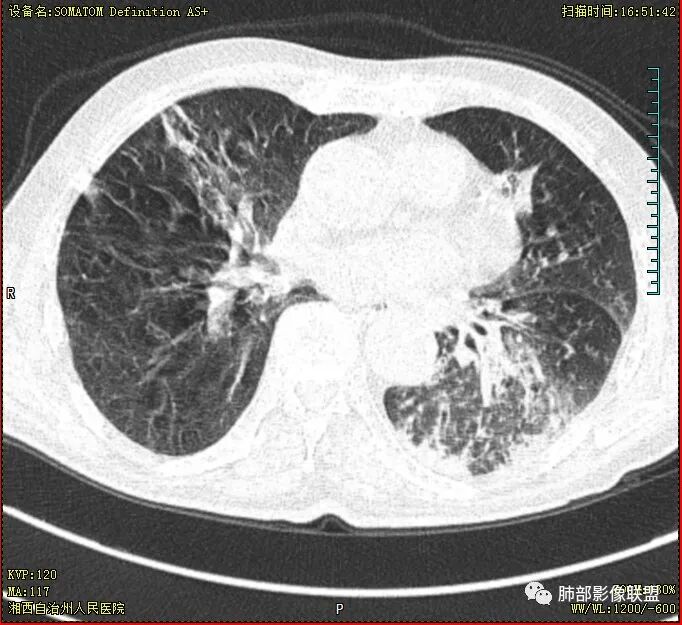

晨读 双肺多发斑片、斑点影,可见树芽征,支气管播散,右肺上叶小空洞,左肺下叶厚壁空洞,内壁较光整,有浅液平,右下叶背段支气管变窄,不均匀强化。结合临床考虑结核并感染,待排除合并肺癌可能。

晨读:老年男性患者,痰中带血伴间断发热2周,体温39.4℃,白细胞、中性粒细胞,CRP增高,Tspot阳性,胸部CT:双肺病变,左肺下叶背段大片实变密度影,边界模糊,内部见空洞形成,空洞内壁总体光滑,有气液平,增强扫描轻度不均匀强化,一月后复查空洞消失,实变影吸收减少,考虑感染性病变,结核伴肺脓肿。

晨读,老年男性,中等病程,咳嗽,痰中带血,发热,主病灶位于左肺下叶空洞,厚壁,偏心,内壁光滑,边界清楚,不均匀强化,内有坏死,考虑结核,内有气液平,周围部分小叶中心结界,好热,白细胞升高,合并感染。结核合并感染,鉴别肺癌合并感染。

老年慢性长期吸烟,痰中带血伴发高热。左下肺大片不均质实变里可见一含气液平厚壁空洞,内壁有坏死物残留,增强可空洞壁明显强化轮廓显示清晰,空洞位于肺门侧,近端支气管壁不规则增厚。两肺散在斑片状影,并见小树芽。18号复查肺窗空洞显示不清,20号用了俯卧位扫描,液体向下流动空洞又显示出来了。左下肺病灶有变小,还是考虑感染性病变,结核合并感染,鉴别鳞癌。

老年患者。左肺下叶厚壁空洞,有液平面。空洞内壁较为光整。病灶的内侧见支气管节段性的变窄扭曲。两肺内,弥漫性的广泛性的播散病灶。考虑感染性病变。肺结核并空洞形成两肺内播散。鉴别诊断-左肺下叶鳞癌。

老年男性,肺气肿,左肺下叶空洞,壁厚薄不均,见液平,下叶支气管阻塞,不均匀强化,伴两肺斑片及树芽影,考虑左肺下叶癌性空洞(鳞癌)并感染及两肺结核

双肺多发结节影,树芽征,小叶中心分布,左肺下叶不规则空洞,洞内壁光滑,见液平,洞壁似与支气管相通,增强扫描明显强化,可见血管造影征。三周左右复查空洞明显缩小。

老年男性,痰中带血,双肺多发点片状阴影,左肺下叶可见空洞影,有液平,不均匀强化,局部低密度区边界不清晰,复查病灶范围缩小,空洞消失,结合病史肿标增高,首选考虑肿瘤合并肺脓肿,鉴别淋巴瘤,结核。

双肺多发点片、索条斑条灶,见多发树丫征,左下肺大片不均质实变,内见一含气液平厚壁空洞,壁厚,内壁有坏死物残留,增强可空洞壁明显强化

,空洞位于肺门侧,近端支气管壁不规则增厚。

首先双肺多灶多形态病灶,考虑结核,聚焦左下肺病灶,空洞,内壁尚光整,有明显液化坏死,增强无明显强化,壁内可见支气管充气征,复查后空洞缩小,首先考虑良性,结核伴脓肿,鉴别鳞癌

胸部CT:双肺多发小斑片、树芽、索条灶,左下肺大片不均质实变,远肺门侧厚壁空洞,气液平,内壁有坏死物残留,增强可空洞壁不均匀强化,近端支气管壁不规则增厚堵塞,实变影内可见与洞壁平行支气管。抗炎3周有缩小。

双肺边界较清楚的斑点状影、树芽征,结合T-SPOT阳性,长病程,体重减轻等,继发性肺结核是应当考虑的,至少作为基础疾病之一。

2.患者发热,中性粒细胞等炎性指标轻度升高,C-反应蛋白高,短期内双肺病灶吸收明显,吸收部分较符合普通感染性病灶,也可以因部分肺泡积血有所吸收。

3.注意到左肺下叶空洞性病灶,腔壁厚度不均,环形强化较为明显,壁间支气管血管影走行,腔内液气平面,这通常见于感染性病灶,如脓肿,经治疗病灶吸收也高度支持病灶主体成分为脓肿。

4.老年男性患者,痰中带血,体重减轻,空洞性病灶壁厚不均疑及肿瘤性病变符合常理。

尽管坏死明显,但穿行血管结构自然,血供如此丰富,鳞癌的判断使人望而却步,腺癌的判断也缺乏有说服力的线索。